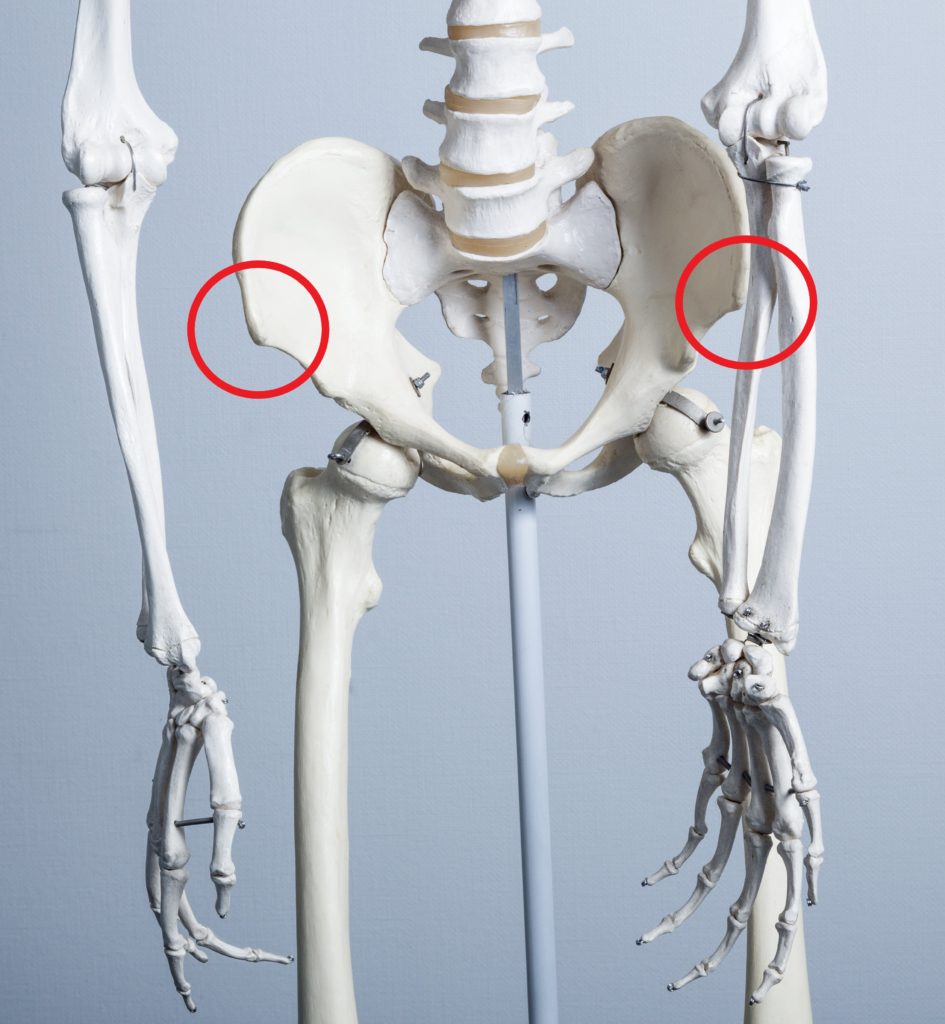

体表だとヘソと上前腸骨棘(赤丸)とを結んだ線(赤線)の真ん中やや外側あたり(黒丸)です。

この黒丸部分がS状結腸です。